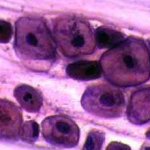

Πινακοθήκη κυτταρολογικών ευρημάτων ΙΙΙ

Οι πινακοθήκες κυτταρολογικών ευρημάτων, έχουν σαν στόχο να εμπλουτίσουν την κυτταρολογική εμπειρία σπουδαστών και ειδικευομένων, όπως ένας άτλαντας.

Παρουησιάζονται λοιπόν τυχαία ευρήματα, από το καθημερινό γυναικολογικό ιατρείο.